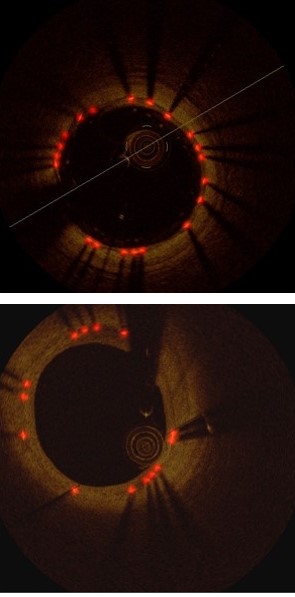

Table 1 and Fig. 3(b) show the detection results of our method at individual stages. Fig. 5(a) shows the two example detection results with various thickness coverage. The Local-Network shows the higher recall while Global-Network achieved better precision results (as shown in Fig. 5(c) and Fig. 5(d)). As exemplified in Fig. 5(e), the proposed method integrated both Local Network and Global-Network and achieved a better consistent performance in recall and precision.

Refer to caption

(a) Image

(b) Label

(c) Locals.

(d) Global.

(e) Ours

Figure 5: Example results of struts detection. Red arrows indicate the detection errors.

Table 1, Fig. 3(b) and Fig. 5 compared the main components of our method individually to quantify their contributions to the final detection results. These results demonstrate that Local-Network has higher recall and we attribute this to the usage of patch-based network to detect all the potential strut candidates. In contrast, Global-Network achieved higher precision for its ability by adding global context, e.g., appearance information, as part of the learning process, which ensures all the detected struts are consistent with the shape of the stent. Table 1, Fig. 3(b) and Fig. 5 also show the advantages from our combination which integrates complementary detection results produced at individual components.